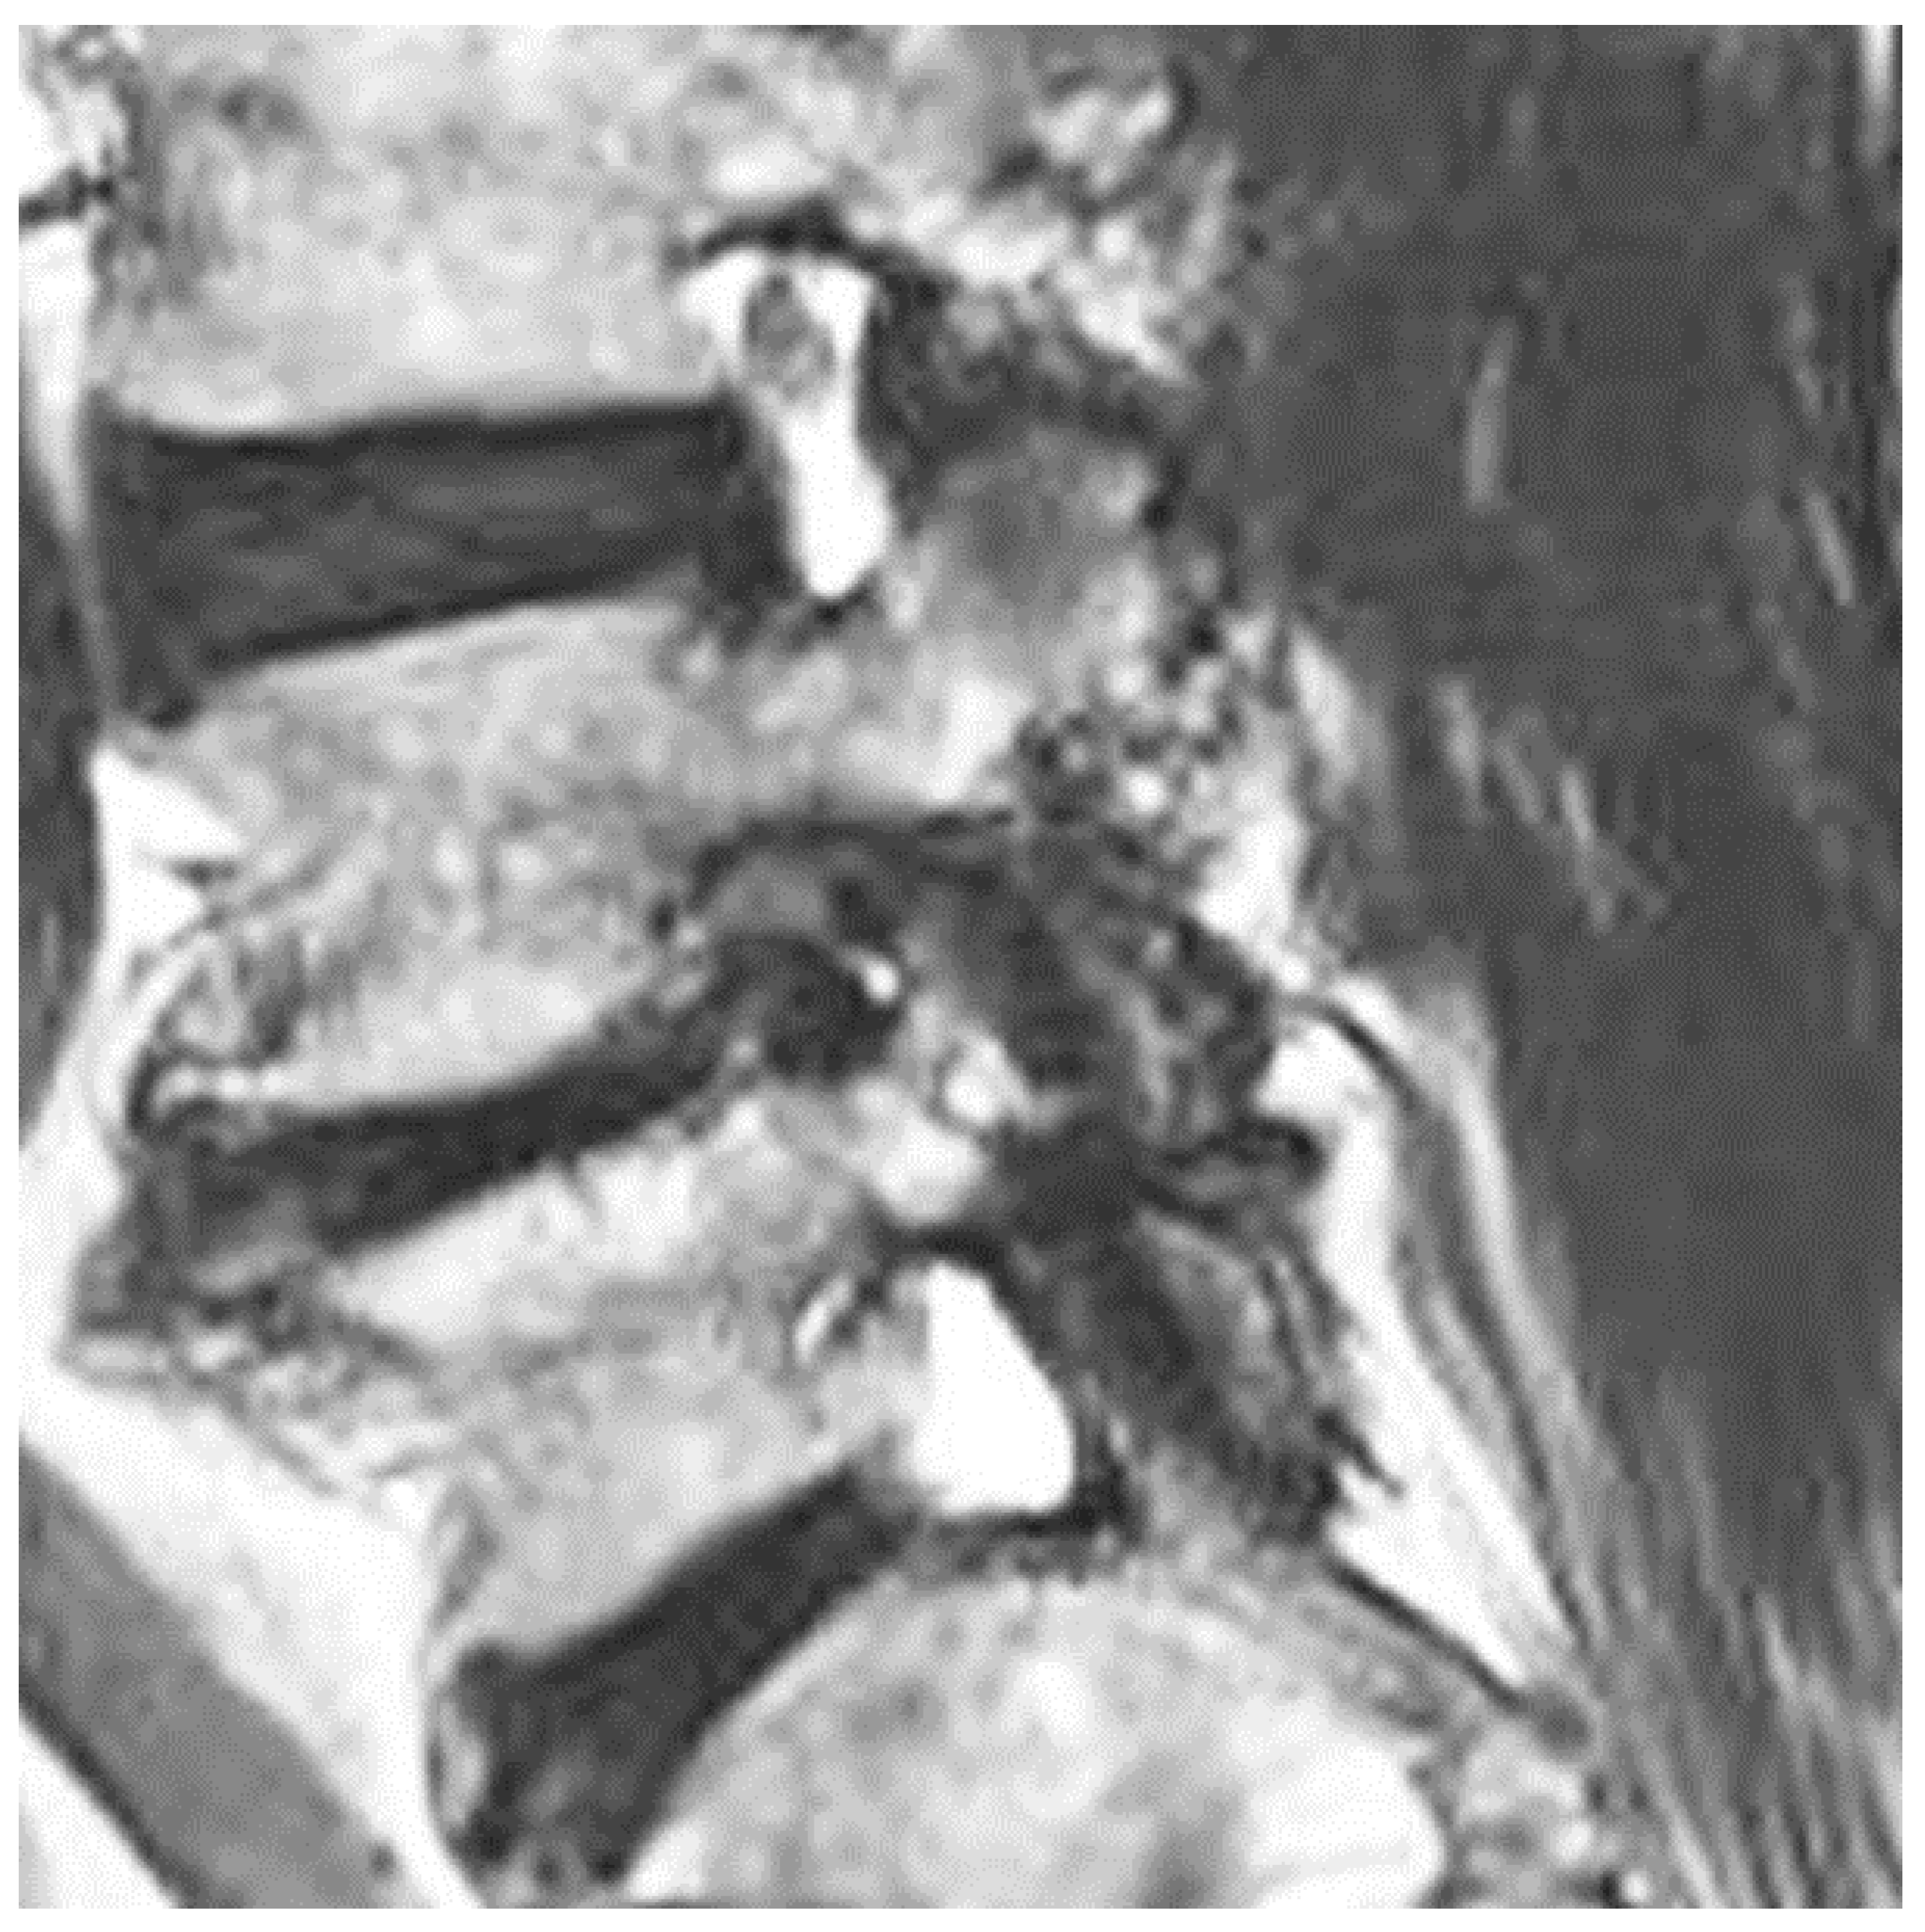

Nanoori Hospital maintained a prospectively collected database of all patients who underwent Endo-TLIF. PHW, YJL and DHK retrospectively reviewed all radiological and clinical data from the database. From the Endo-TLIF data base, we included symptomatic patients who suffered back pain and lumbar claudication who failed a minimum of 6 weeks of conservative treatment. They had the following clinical diagnoses: (1) grade 2 and below spondylolisthesis; (2) spinal stenosis with instability; (3) end-stage degenerative disc disease with severe foraminal stenosis. They had radiological parameters as follows: (1) severe disc collapse with mid sagittal lumbar spine Computer Tomographic (CT) middle disc height shorter than 5 mm; and (2) Magnetic Resonance Imaging (MRI) of Grade 3 Classification of Foraminal Stenosis by Lee et al. [17] (Figure 2). We excluded patients who had spinal fusion surgery due to trauma, revision surgery, tumor, infection, pseudarthrosis, congenital spinal deformity, sagittal malalignment and coronal deformity with more than a 20-degree coronal curve.

MRI lumbar scans for all patients with mid sagittal CT lumbar spine mid disc heights of less than 5 mm who had symptomatic foraminal stenosis were pre-operatively evaluated, and coincidentally, all of these patients had grade 3 Lee classification foraminal stenosis (Figure 2) [17].

Figure 2. Mid right foraminal MRI of lumbar spine. It showed severe grade 3 Lee et al. foraminal stenosis with morphological change of right L4 exiting nerve root in right L4/5 foramen.

Brainsci 10 00373 g002